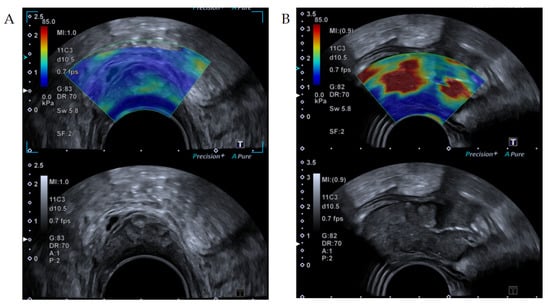

2.1.2. Shear Wave Elastography